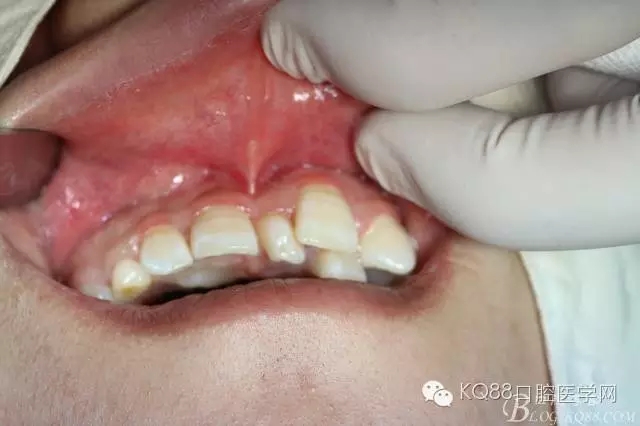

患者、田xx、女、17歲、主訴:右側(cè)門牙松動(dòng),要求治療。??茩z查:11松動(dòng)Ⅰ度,11與21之間有一多生牙,CBCT檢查:13位于11根尖區(qū),并壓迫11牙根吸收約1/2,53滯留、正畸科建議:拔除11、并正畸牽引13到11位置,然后行13牙冠改形。患者不同意該方案,僅考慮拔除13,防止11牙根進(jìn)一步吸收。醫(yī)患溝通后,同意患者的要求、拔除埋伏13,簽知情同意書。

圖1.患者11與21之間有一多生牙、53滯留、13未見萌出、11松動(dòng)Ⅰ度